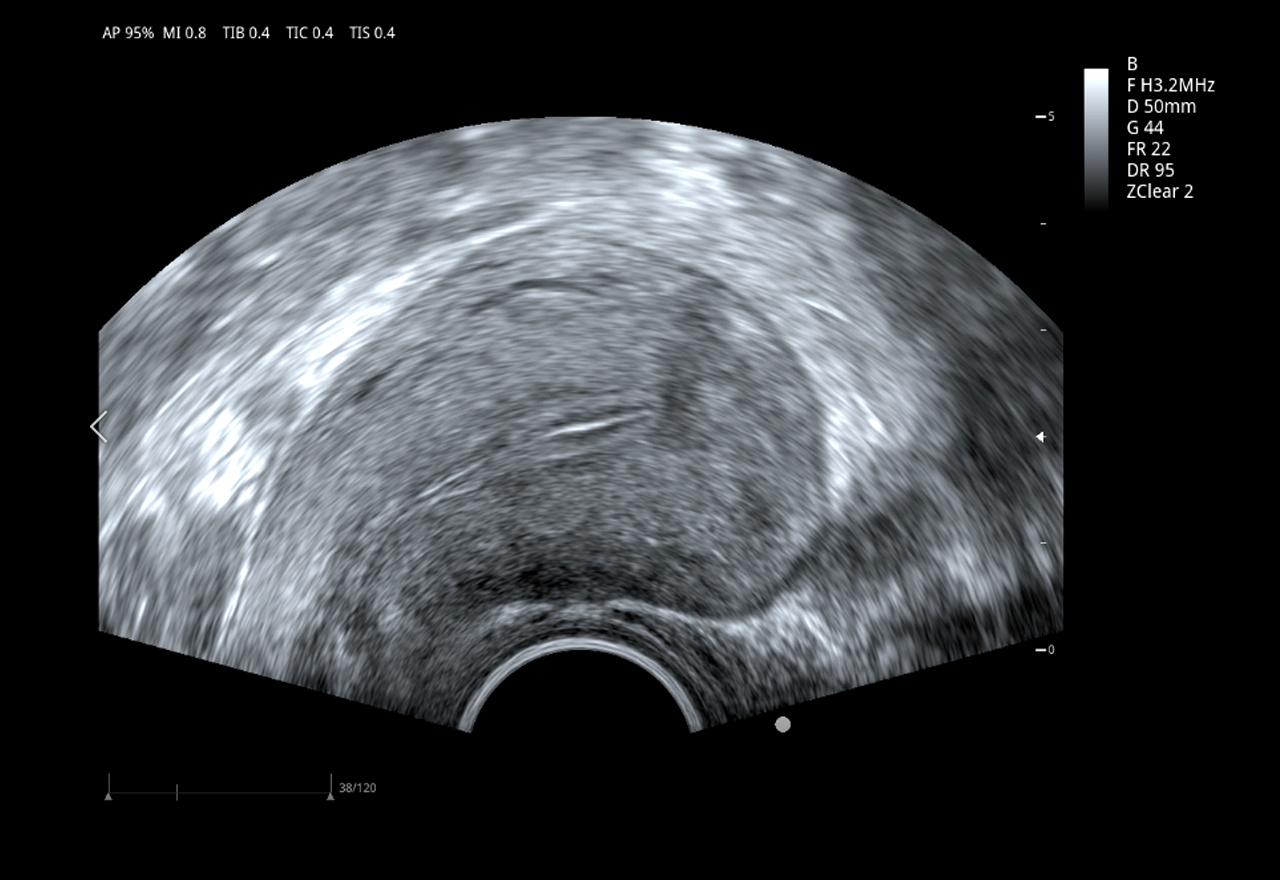

Imágenes clínicas extraordinarias